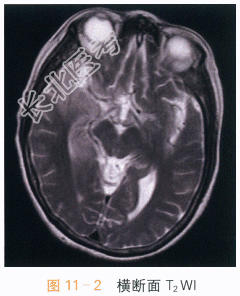

影像学资料如图11-1~图11-4所示。

读片分析:两侧岛叶及右侧颞叶可见片状异常信号影,右侧为著,呈T₁WI低信号,T₂WI、FLAIR高信号影,增强后可见轻度强化,未侵及两侧基底节区。两侧岛叶及右侧颞叶异常信号灶,右侧为著,结合患者临床表现及其它检查考虑病毒性脑炎可能。